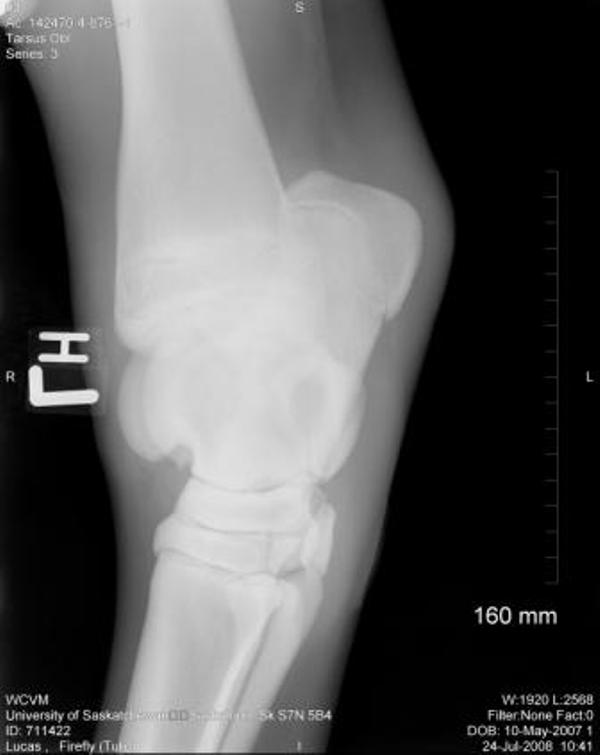

Right Stifle:

There is a fragmentation of the medial intercondylar eminence of the proximal right tibia. This is most likely an osteocchonDrOsis dissecans lesion. No other lesions are identified.

Thank you so much for your assistance, it is really appreciated!! I finally have the cd of the x-rays and will be posting them here. Again, thank you!! The first 2 are stifle pictures, the rest are of the hock.

Stifle

Right stifle

Thanks Dr. O!! I really appreciate your taking a look at this. I do have Dr. Rantanen's report which is as follows:

Interpretation:

The most proximal portion of the right medial tibial spine was separated by an irregular fracture line. The fragment was still close to its anatomic position.

There was no soft tissue swelling or secondary joint disease present at this time.

Comment:

With the absence of clinical signs of lameness, normal flexion and no soft tissue swelling at this time, this fracture most likely occurred at a young age. It may be an incidental finding in this horse. Success in training would confirm that this fracture most likely occurred at a young age and may be tolerated without surgical intervention.